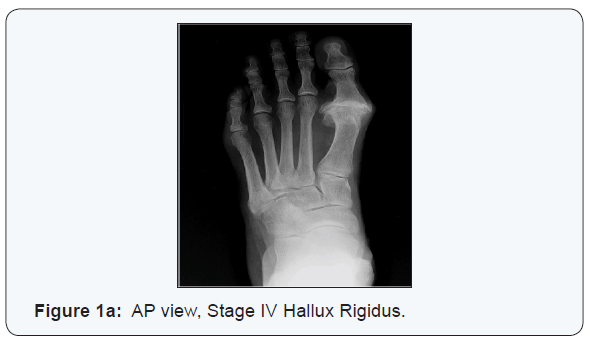

Motion loss of 50% to 75% is present. In Grade III, pain is usually constantly exacerbated by plantar flexion and dorsiflexion of the hallux. Subchondral cysts and sesamoid bone involvement are radiographically evident, with 75% to 100% loss of motion. In Grade IV, similar findings of Grade III are seen, but patient’s present with pain throughout the mid-range of motion on clinical examination [3] (Figures 1a & 1b). Patients presenting with Hallux limitus/rigidus may initially be managed with non-operative treatment. Stiff-soled shoes, non-steroidal anti-inflammatory drugs, corticosteroid injections and orthotics are commonly employed. Surgical options include but are not limited to cheilectomy, osteotomy, arthroplasty and arthrodesis. This study looked at first metatarsal phalangeal joint fusions with cannulated crossing screws and a dorsal, low profile neutralization plate (Flower Orthopedics, Horsham PA) in association in association with early weight bearing.